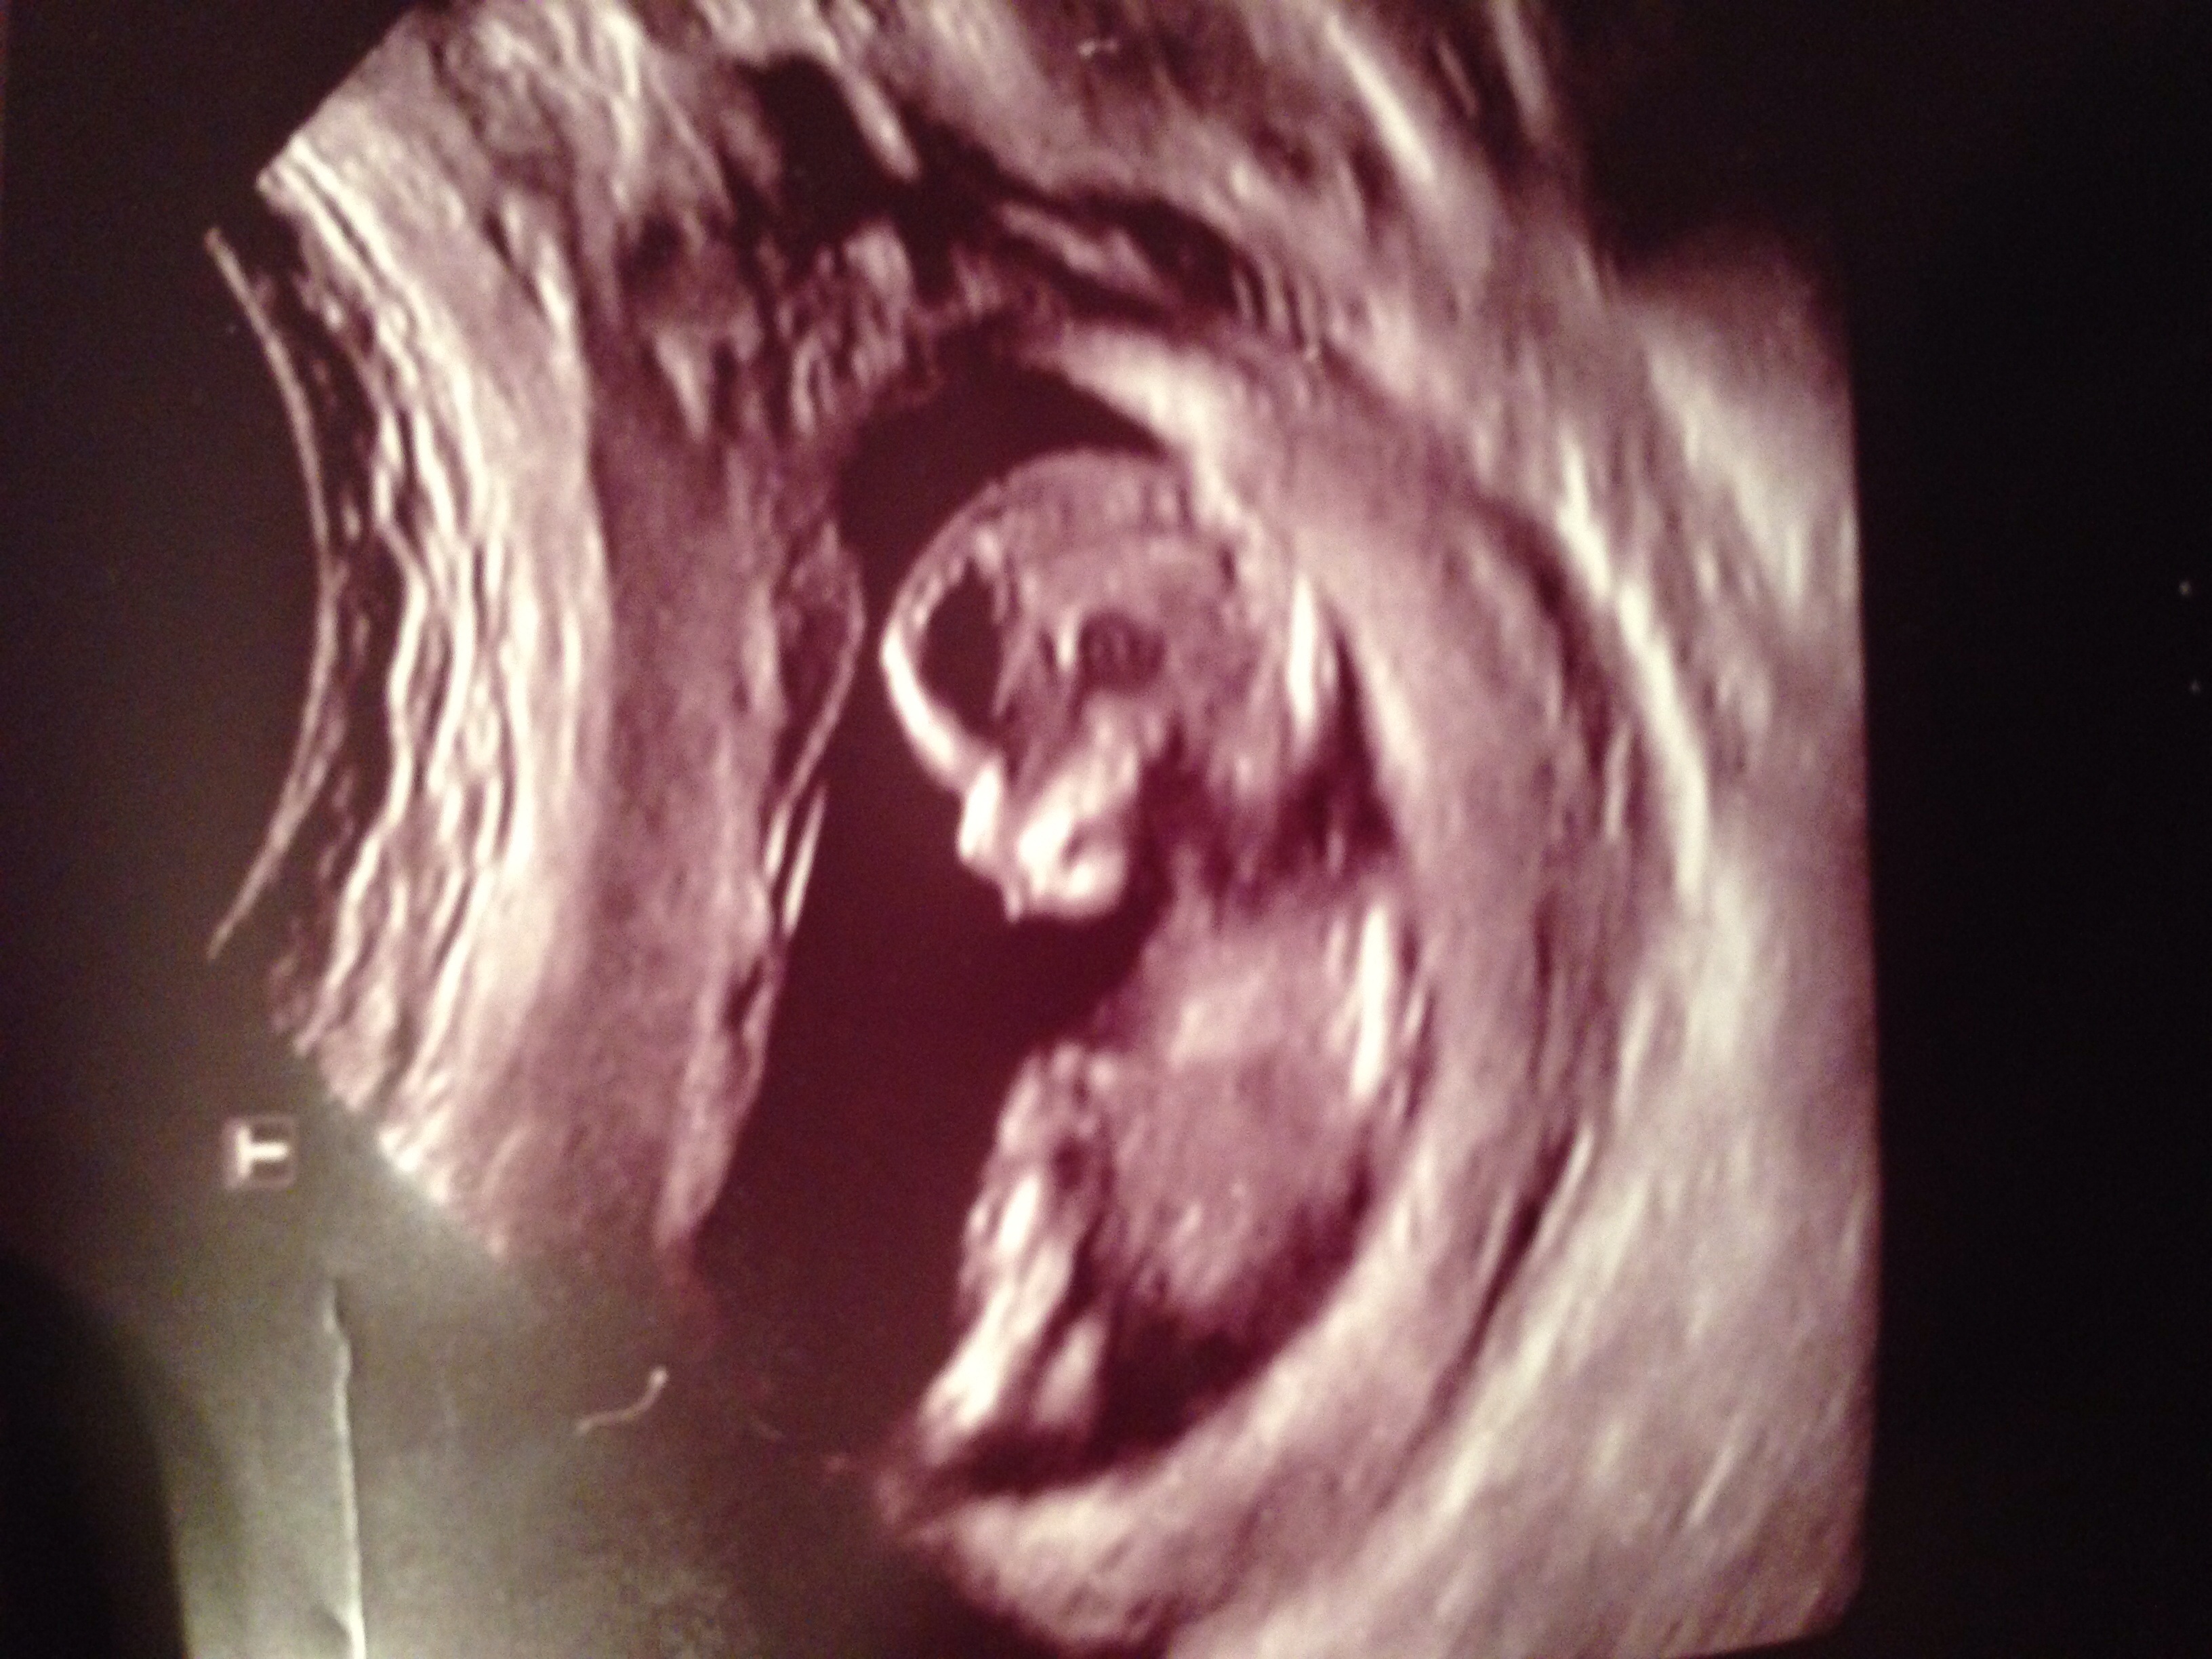

I'm not sure if any of these pictures have any gender clues, but could you please take a look and guess?! Thank you!!

I think girl for you!

I would guess girl too :)

Girl

But going by your pics... the first 2 aren't definitive, the 3rd looks very girly and the 4th looks sort of boyish.